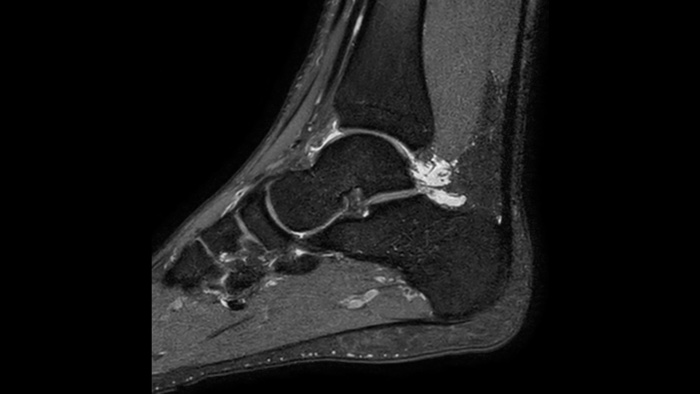

Confianza diagnóstica Ofrece una resolución espacial hasta un 60% más alta en el mismo tiempo de escaneo. 4

Confianza diagnóstica Amplíe su capacidad de obtener imágenes excelentes en todas las áreas clínicas. Vea cómo se benefician sus compañeros.